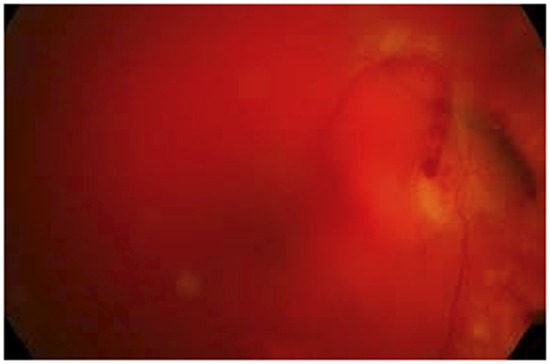

Hemorragia vítrea que impide la visualización del fondo.

Sospecha de desprendimiento de retina traccional (DRT).